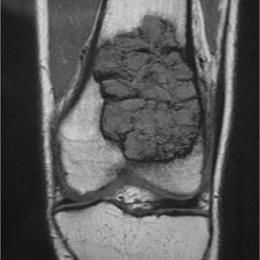

• • The work-up often consists of a physical examination, X-rays, CT scans, MRI, and sometimes bone scans are required.

Radiographic imaging is used to help form a diagnosis. These include X-Ray, MRI, CT and Bone Scans

An example of a Giant Cell Tumor X-Ray is shown.